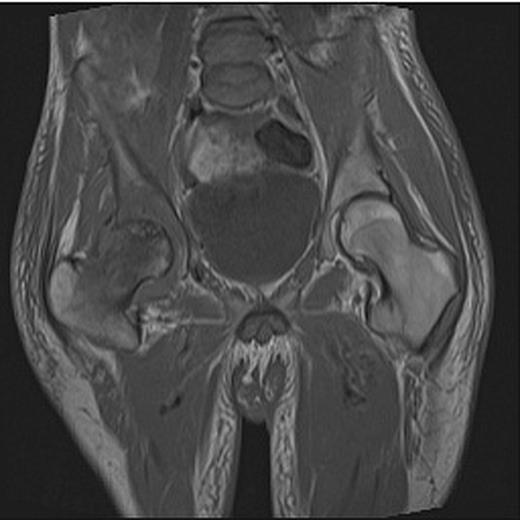

At presentation the patient was afebrile and haemodynamically stable. He was assessed by both the medical and surgical teams at a district general hospital and commenced on intravenous metronidazole and flucloxacillin for a presumed groin abscess. On examination, a pansystolic murmur was heard across precordium with no peripheral stigmata of endocarditis and a discharging sinus in the right groin with a grossly limited range of movement of the right hip. Blood tests revealed a white cell count (WCC) of 7.1 (neutrophils 5.8) and C-reactive protein (CRP) of 146. A pelvic radiograph revealed evidence of degenerative change in the right hip (Fig. 1) and following review by the local orthopaedic team an MRI was carried out confirming avascular necrosis of the right femoral head with an associated collection (Fig. 2).